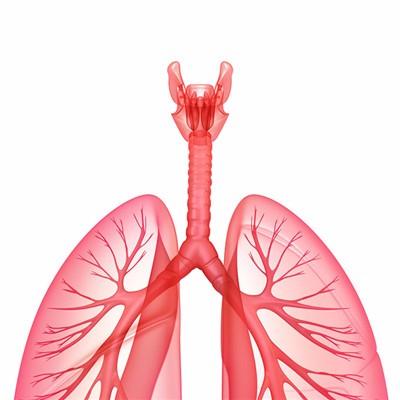

My brother kept coughing these two days, and he also said that he had chest tightness and abdominal pain, and felt that the situation was not right. We went to the hospital for examination. As a result, the doctor said that his brother was diagnosed with lung cancer, and timely treatment was the most important thing. Next, I'd like to talk about the method of completely cured lung cancer?

First, chemotherapy is the main treatment for lung cancer, more than 90% of lung cancer need chemotherapy. The curative effect of chemotherapy on small cell lung cancer is positive in both early and late stage, and even about 1% of early small cell lung cancer is cured by chemotherapy. Chemotherapy is also the main treatment for non-small cell lung cancer. The tumor remission rate of chemotherapy for non-small cell lung cancer is 40% - 50%.

Second, radiotherapy is the best for small cell lung cancer, followed by squamous cell carcinoma and adenocarcinoma. The radiation field of lung cancer should include the mediastinum of primary tumor and lymph node metastasis. At the same time, it should be supplemented by drug treatment. Squamous cell carcinoma has moderate sensitivity to radiation, the lesions are mainly local invasion, metastasis is relatively slow, so radical treatment is often used. Adenocarcinoma is not sensitive to radiation and easy to metastasize, so radiotherapy alone is rarely used.

Third: according to the different purposes of treatment, it can be divided into radical treatment, palliative treatment, preoperative neoadjuvant radiotherapy, postoperative adjuvant radiotherapy and intracavitary radiotherapy. Surgical treatment is the first choice and the most important treatment for lung cancer, and it is also the only treatment that can cure lung cancer. The purpose of surgical treatment of lung cancer is: to completely remove the primary focus and metastatic lymph nodes of lung cancer, to achieve clinical cure; to remove most of the tumor, to create favorable conditions for other treatment, namely tumor reduction surgery.

For patients with lung cancer, cough and chest tightness will often appear. If not treated in the early stage, hemoptysis will appear in the later stage. Surgery and chemotherapy can be used to control the proliferation and differentiation of cancer cells. In addition, some immunity enhancing drugs can also be taken.